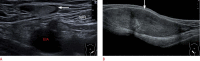

Inguinal hernia is the most prevalent type of abdominal wall hernia. Indirect inguinal hernia is twice as common as direct inguinal hernia. Computed tomography and magnetic resonance imaging can be used to evaluate inguinal hernia, but these modalities are greatly limited by their cost and availability. Ultrasonography has emerged as the most convenient imaging tool for diagnosing inguinal hernia due to its advantages, such as portability and absence of radiation. The present pictorial review presents an overview on the use of ultrasonography in the evaluation of inguinal hernia with a particular emphasis on the regional anatomy, relevant scanning tips, identification of subtypes, postoperative follow-up, and diagnosis of pathologies mimicking inguinal hernia.